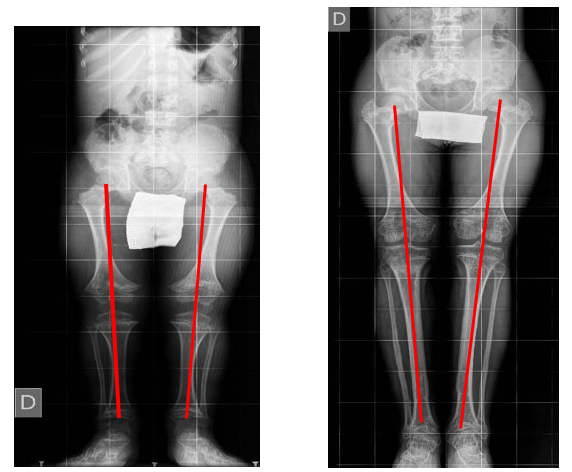

a) Mechanical axis deviation (MAD) (Figure 1), measured on long standing radiographs preoperatively and at the last follow-up

Figure 1: Mechanical Axis Deviation on Long Standing Preoperative and Postoperative Radiograph